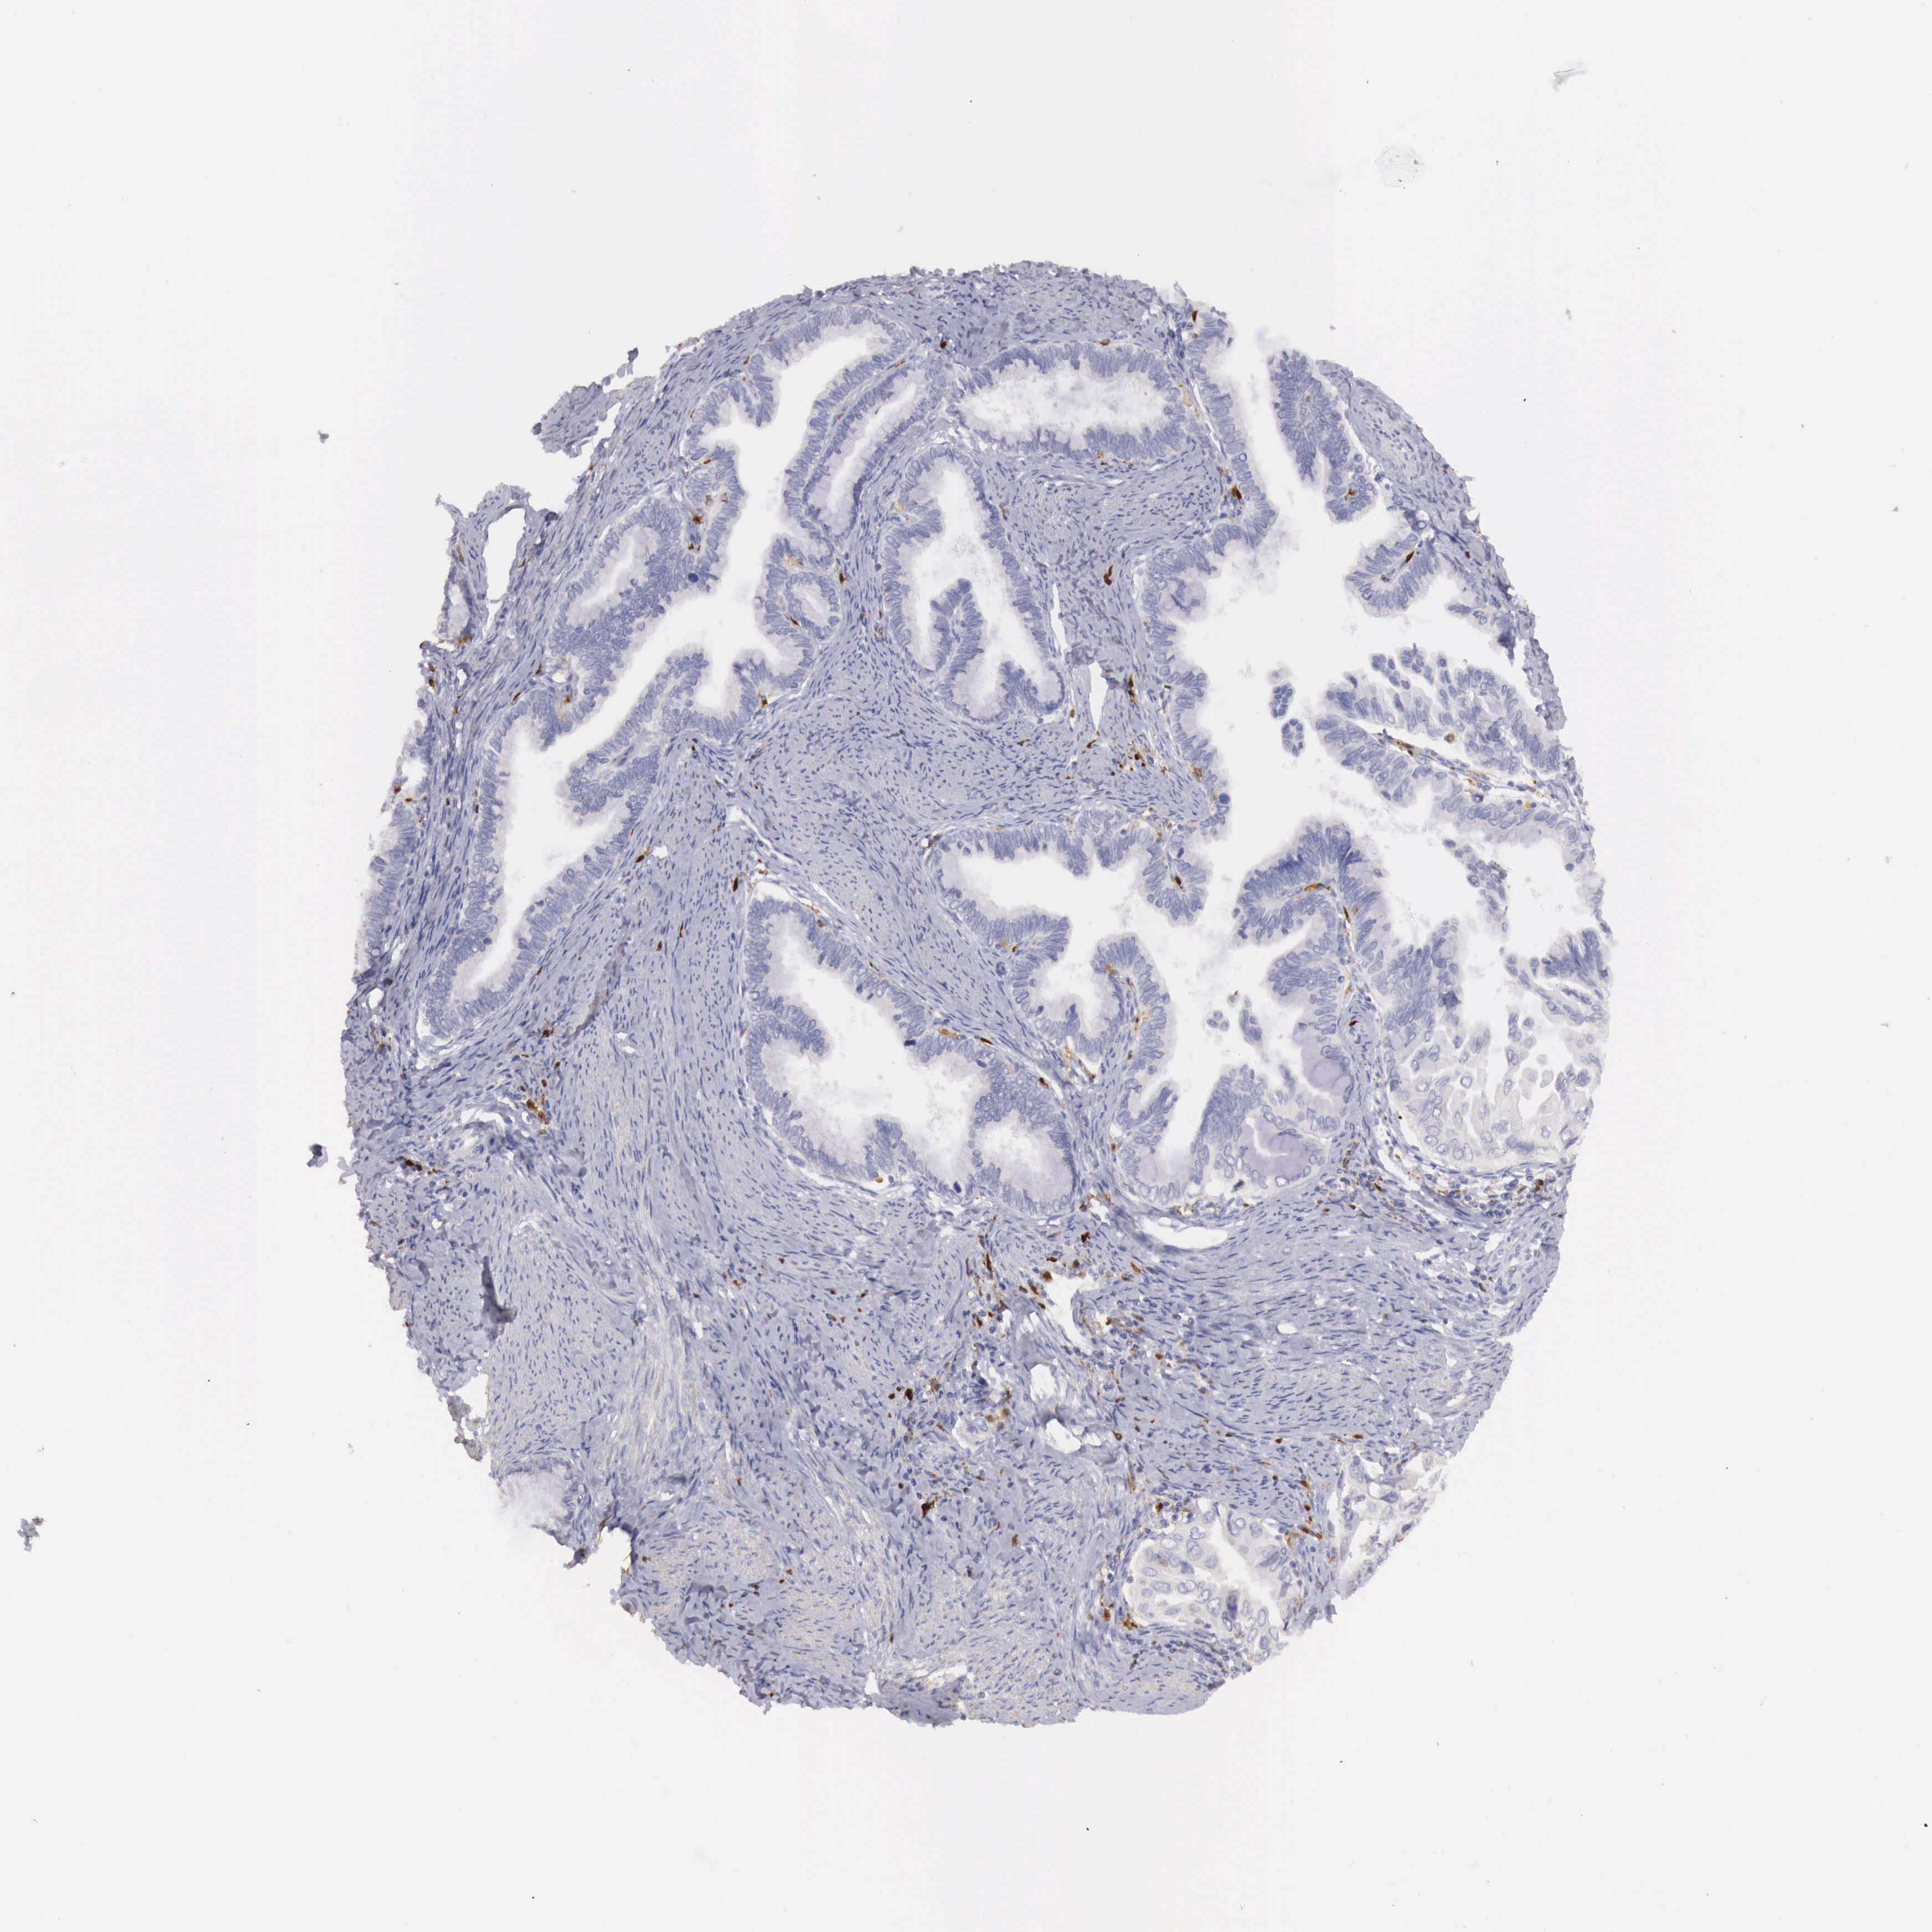

CERVICAL CANCER - Protein expressioni

A mouse-over function shows sample information and annotation data. Click on an image to view it in a full screen mode. Samples can be filtered based on level of antibody staining by selecting one or several of the following categories: high, medium, low and not detected. The assay and annotation is described here.

Note that samples used for immunohistochemistry by the Human Protein Atlas do not correspond to samples in the TCGA dataset.

Antibody stainingi

Antibody staining in the annotated cell types in the current human tissue is reported as not detected, low, medium, or high, based on conventional immunohistochemistry profiling in selected tissues. This score is based on the combination of the staining intensity and fraction of stained cells.

Each image is clickable and will lead to virtual microscopy that enables deeper exploration of all samples and also displays staining intensity scores, fraction scores and subcellular localization as well as patient and tissue information for each sample.

Antibody HPA000428

Antibody HPA000522

Staining

High

Medium

Low

Not detected

Intensity

Strong

Moderate

Weak

Negative

Quantity

>75%

75%-25%

<25%

None

Location

Nuclear

Cytoplasmic/membranous

Cytoplasmic/membranous,nuclear

Adenocarcinoma, NOS

Squamous cell carcinoma, NOS